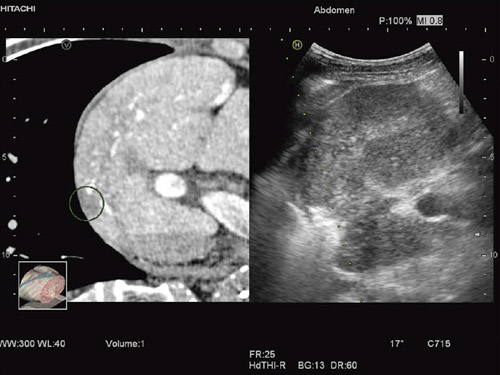

CT/MRI/USの画像情報から,観察中の超音波画面に対応するMulti-Planar Reconstruction(MPR)像をリアルタイムに同時表示する“Real-time Virtual Sonography(RVS)”について紹介する。

本技術は,日立が2004年に世界で初めて開発し1),2),超音波診断装置と他モダリティの欠点を補い,マルチモダリティの画像情報を融合させる技術である。肝がんの治療手段として普及しているRadio Frequency Ablation(RFA)などの臨床現場で導入されているシステムである3)

超音波診断装置による走査で得られた超音波画像が表示されるのに同期して,プローブの位置と角度を検出し,それに対応した断面像をCT/MRI/USのボリュームデータからリアルタイムに再構成してMPR表示を行う(図1)。